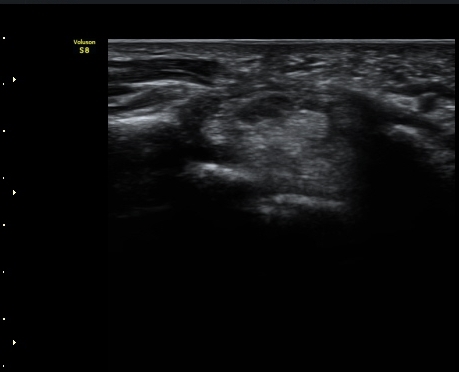

¼ö±Ù°ü¸»´Ü(trapezium ±âÁØ) Á¤Á߽Űæ Ⱦ´Ü¸é°Ë»ç¿¡¼­ Á¤Á߽ŰæÀÇ Àú¿¡ÄÚ ºÎÁ¾ÀÌ °üÂûµÈ´Ù(±×¸² 3)

ÀÌ´Â Åë»óÀûÀÎ ¼ö±Ù°üÁõÈıº¿¡¼­ º¸ÀÌ´Â ¾ç»ó°ú ´Ù¸¥ ¸ð½ÀÀÌ´Ù.